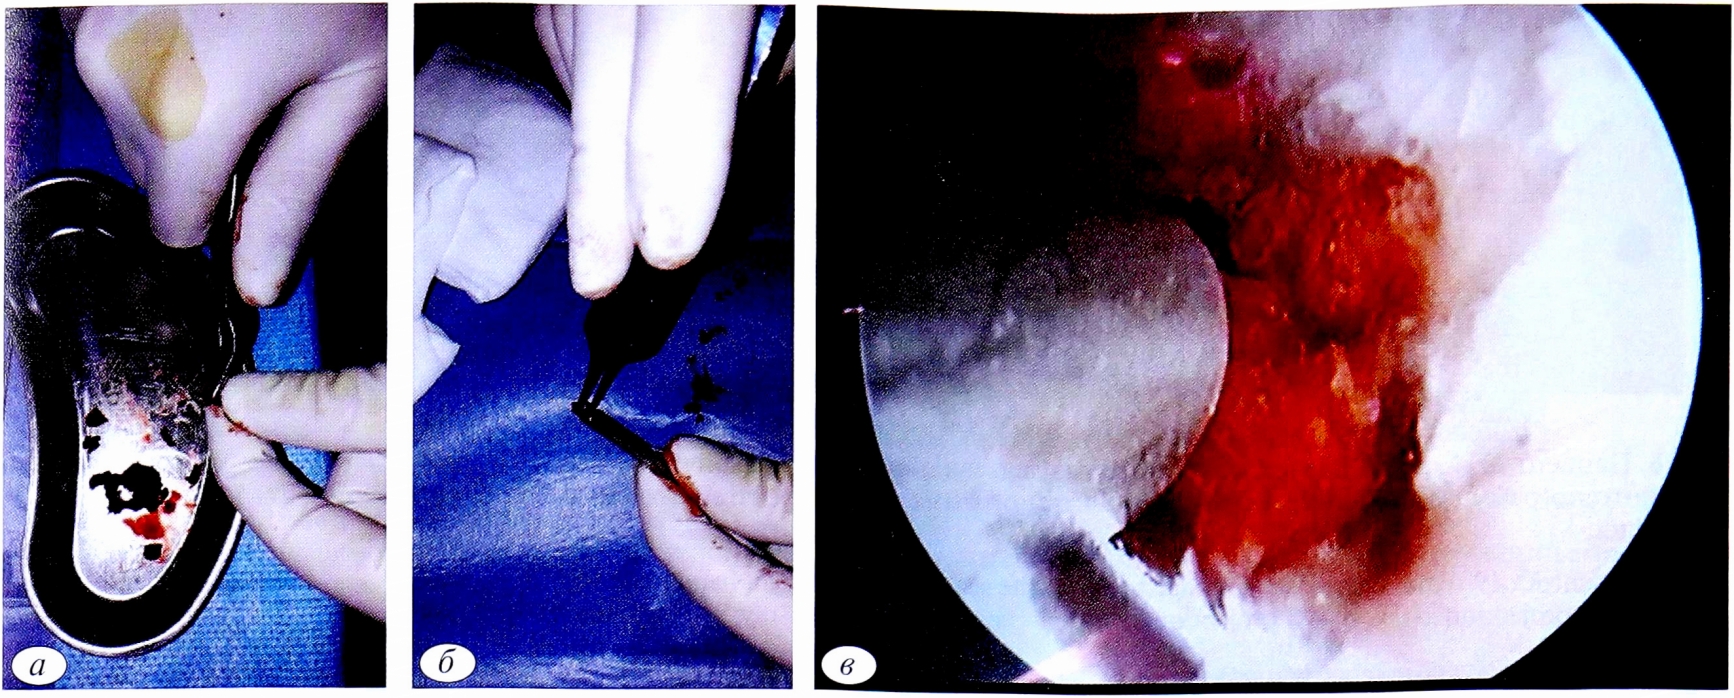

Через лучевой среднезапястный порт (ЛуСП) при помощи кусачек производили удаление рубцовой ткани, резекцию ложного сустава ладьевидной кости (рис. 3 а, б).

Рис. 3. Дебридмент зоны ложного сустава (а); внешний вид ладьевидной кости после резекции ложного сустава (б).

Fig. 3. Pseudoarthrosis zone debridement (a); appearance of the scaphoid after resection of pseudoarthrosis (b).

Далее под артроскопическим и рентгеновским контролем проводили 3 спицы: одна — осевая, проходящая сразу через дистальный и проксимальный отломки ладьевидной кости. Две другие спицы проходили только через дистальный отломок. Затем из крыла подвздошной кости брали губчатый костный трансплантат по типу «стружки», средний размер одного костного трансплантата — 0,2×0,2 см (рис. 4, а). Шахту заполняли костными трансплантатами (см. рис. 4, б) и вводили в зону ложного сустава (см. рис. 4, в) через ЛуСП.

Рис. 4. Обработка губчатого костного аутотрансплантата (а); заполнение шахты костной «стружкой» (б), введение костных трансплантатов в зону ложного сустава (в).

Fig. 4. Fragmentation spongy bone (a); bone graft filling (b); insertion of a bone graft into the pseudoarthrosis zone (c).